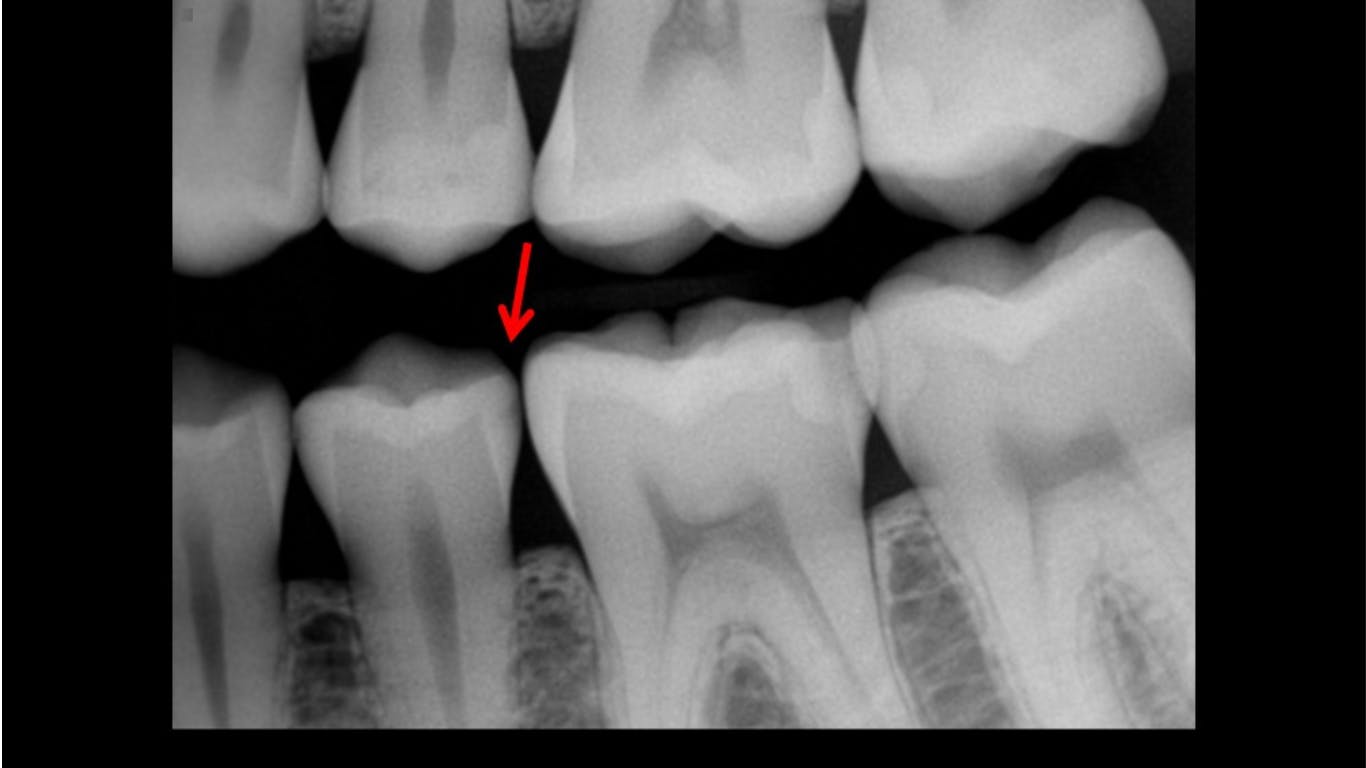

Experienced dentists, including myself, often compare current digital radiographic images with analog film images of the past. It is easily apparent to the naked eye that analog film shows more detail and accuracy. This deficiency can be problematic relative to identifying initial caries and many other features. Enhancing the digital images helps interpretation of anatomy and restorations but does not satisfy the challenge. Typical general dentists and hygienists make many radiographic images per day. Misinterpretation of images and lack of proper treatment plans and treatment are often the result (figures 1–3).